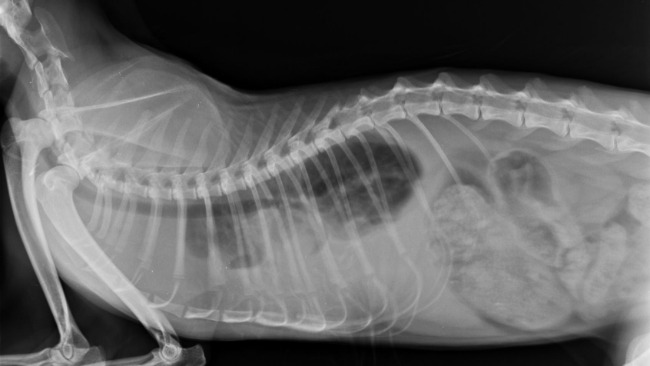

Korek, 2,5-letni kot z Dolnego Śląska, znalazł się w dramatycznej sytuacji zdrowotnej z powodu ropopiersia. Początkowo pojawiły się objawy kaszlu i trudności z oddychaniem. Mimo podjętej antybiotykoterapii, jego stan pogorszył się, co przejawiało się brakiem apetytu, apatią, a przede wszystkim bardzo męczącymi, astmatycznymi napadami kaszlu.

Po przewiezieniu do Warszawy i przeprowadzeniu szeregu badań diagnostycznych, takich jak badanie rentgenowskie, USG klatki piersiowej oraz echo serca, potwierdzono diagnozę ropopiersia - sytuacji, w której gromadzi się ropny wysięk między płucami a sercem.

Aktualnie Korek przebywa w szpitalu, poddawany intensywnej terapii, obejmującej dożylną antybiotykoterapię, drenaż opłucnej oraz regularne płukanie klatki piersiowej.